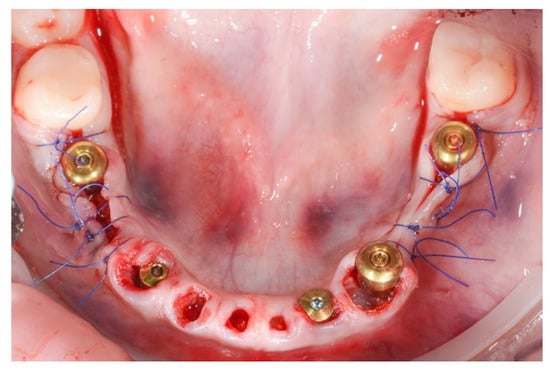

For the mandibular arch, five MIS V3 implants were inserted with guided surgery in the position of 36, 34, 32, 43 and 45, all with 40 Ncm primary stability. We used three MU abutments and two Connect abutments for a passive fit of the future screw-retained bridge and also to have the benefits of the one abutment one time concept.

The PET technique was used for the remaining mandibular incisors and canines after previous endodontic treatment (Figure 12).

Figure 12.

Post-operative aspect of mandibular implant placement and PET for 71, 72, 73, 81, 82 and 83.

On the second day, an immediate PMMA screw-retained provisional restoration was inserted to preserve the gingival margins and to guide the emergence profiles, as well as to ensure the patient’s esthetics and function during the healing period (Figure 13a,b).

Figure 13.

PMMA screw-retained second-day provisional bridge (a) on the stone model and (b) an intraoral view.